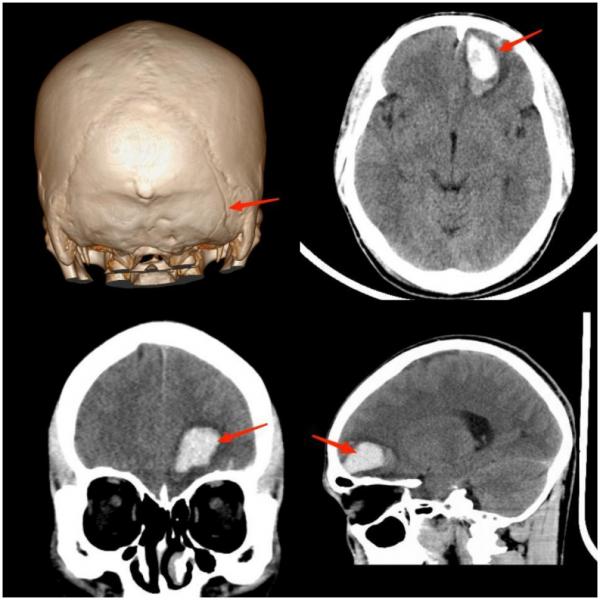

(上图为颅骨骨折并颅内出血)

常见原因:多因球员在奋力争顶球时与对方球员的头或腿部相撞,或冲顶攻门时头撞到门柱而受伤,以颅面骨骨折及颅内出血多见。因此,常会看到两名球员为争抢头球时头部撞在一起倒地不起的画面。